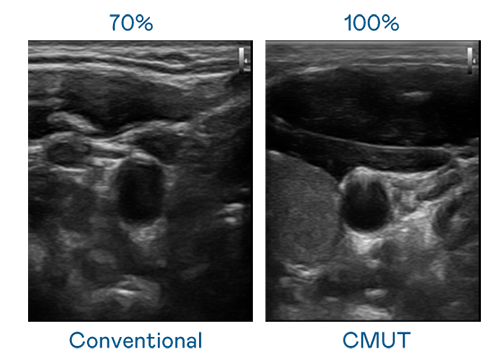

CMUT 技术是一种用电容式微机电元件来产生超音波讯号的技术。与传统 PZT 压电式技术相比,CMUT 频宽增加 30%,更宽频的超音波讯号让影像解析度大幅提升,是实现高影像品质医疗超音波扫描、促进精准医疗发展的关键技术。

大频宽带来超清晰影像

超音波影像的解析度高低,首先取决于探头能发出的讯号频宽。jbo竞博 CMUT 可提供高清晰的超音波讯号,提供高频宽、高灵敏度、影像纹理细节更高的超音波影像,协助医护人员缩短影像判读时间及利用精准的医疗影像进行诊断。